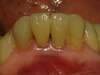

Cas N°2